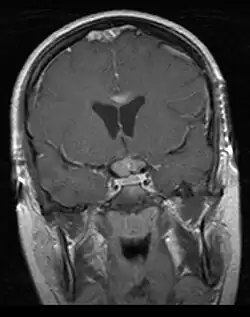

• Mainly located in midline structures, suprasellar region or pineal gland, also basal ganglia and hypothalamus

Location